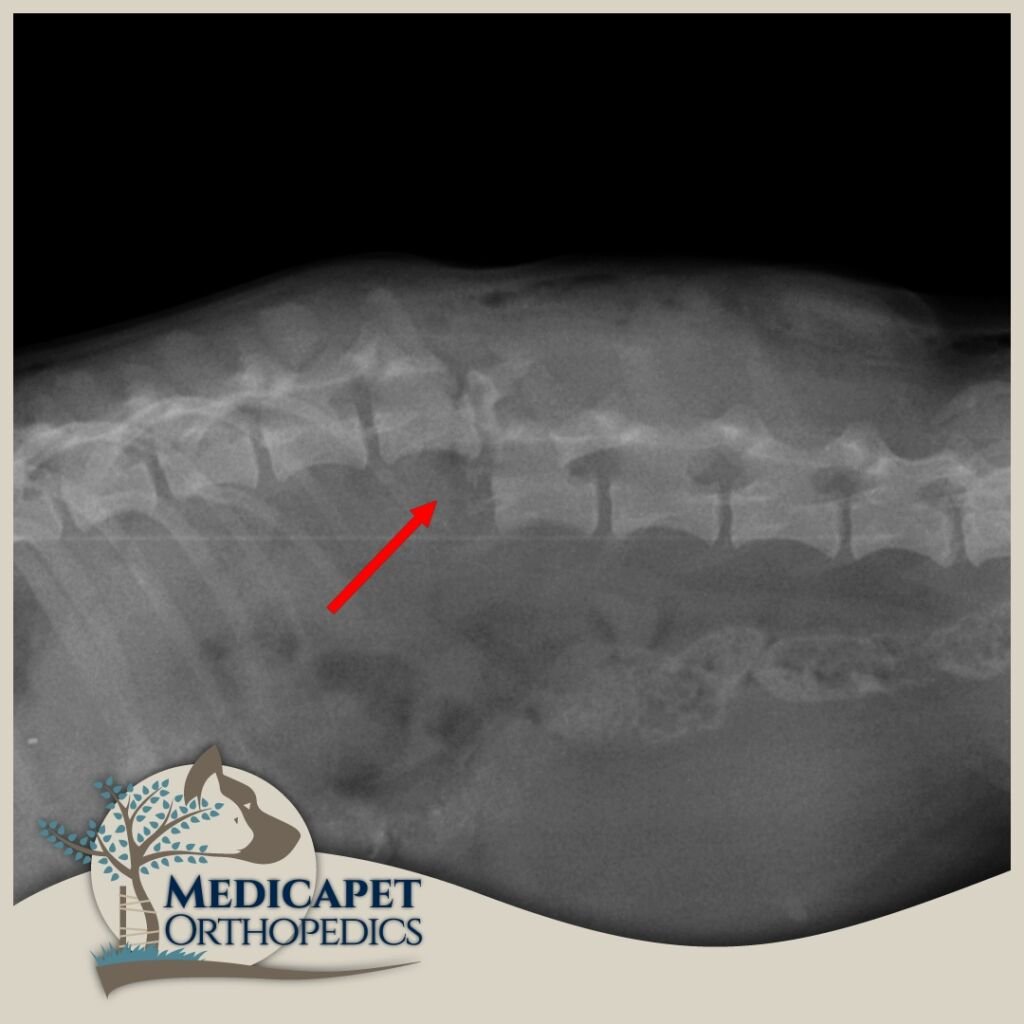

Kemik dokulara paralel seyreden ya da onların içinde bulunan sinir yapıları, kemik hasarlarıyla birlikte zarar görebilir. Yumuşak yapılı sinir dokuları en küçük travmaya karşı hassastır ve korunmaya ihtiyaç duyar. Beyin ve omurilik gibi organlar kafatası ve omurga tarafından korunur, bu nedenle kemik dokuların tedavi ve onarımı sinir dokusuna zarar vermeden yapılmalıdır. Ayrıca bazı sinir hastalıklarında da (örneğin tümörler) kemik dokuya müdahale gerekebilir. Bu yüzden nöroloji ve ortopedi yakından ilişkilidir.

Sinir sistemi; Merkezi Sinir Sistemi (beyin, beyincik, beyin sapı, omurilik) ve Periferik Sinir Sisteminden (gangliyonlar, sinirler, sinir uçları) oluşur. Kliniğe başvuran hastaların çoğunda trafik kazaları, düşme, saldırılar gibi nedenlerle omurga kırıkları, kafatası travmaları veya felç durumları görülmektedir. Bazı ırklarda genetik yatkınlık da omurga sorunlarına yol açabilir.